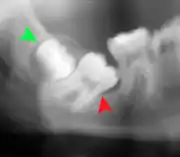

Impacted wisdom teeth are classified by their direction of impaction, their depth compared to the biting surface of adjacent teeth and the amount of the tooth's crown that extends through gum tissue or bone. Impacted wisdom teeth can also be classified by the presence or absence of symptoms and disease. Screening for the presence of wisdom teeth often begins in late adolescence when a partially developed tooth may become impacted. Screening commonly includes a clinical examination as well as x-rays such as panoramic radiographs.

Impacted wisdom teeth are classified by the direction and depth of impaction, the amount of available space for tooth eruption, and the amount of soft tissue or bone (or both) that covers them. The classification structure helps clinicians estimate the risks for impaction, infections and complications associated with wisdom teeth removal.[6] Wisdom teeth are also classified by the presence (or absence) of symptoms and disease.[7]

Impacted wisdom teeth are often described by the direction of their impaction (forward tilting, or mesioangular being the most common), the depth of impaction and the age of the patient as well as other factors such as pre-existing infection or the presence of pathology (cysts, tumors or other disease).[5]: 143–144 Each of these factors is used to predict the difficulty (and rate of complications) when removing an impacted tooth, with age being the most reliable predictor[8] rather than the orientation of the impaction.[9]

If the tooth cannot be assessed with clinical exam alone, the diagnosis is made using either a panoramic radiograph or cone-beam CT. Where unerupted wisdom teeth still have eruption potential several predictors are used to determine the chance of the teeth becoming impacted. The ratio of space between the tooth crown length and the amount of space available, the angle of the teeth compared to the other teeth are the two most commonly used predictors, with the space ratio being the most accurate. Despite the capacity for movement into early adulthood, the likelihood that the tooth will become impacted can be predicted when the ratio of space available to the length of the crown of the tooth is under 1.[5]: 141